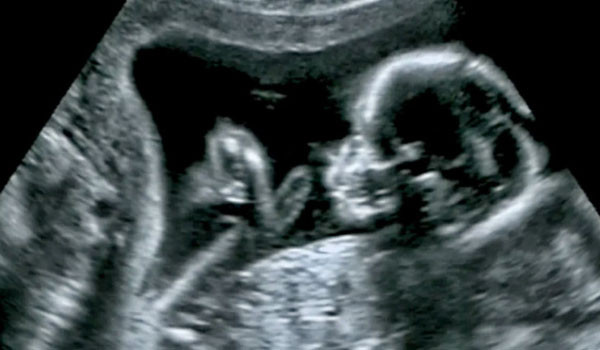

Abone OlDoktorlar, ABD'nin Boston kentinde ülkenin tıp tarihine geçecek bir ameliyata imza atarak anne karnındaki bebeğe beyin ameliyatı gerçekleştirdi. Louisiana'da yaşayan Derek ve Kenyatta Coleman çifti, rutin kontrol için gittikleri hastanede doktorların olağan dışı bir şey fark ettiğini öğrendi.

ABD yerel basınının aktardığına göre doktorlar, bebeğin beyninin içinde nadir görülen bir kan damarı anormalliği olan vasküler malformasyon olduğunu keşfetti. Bebeğin beynini gözlemleyen doktorlar, malformasyonun tehlikeli bir biçimde büyüdüğünü aktardı.

Çiftin onay vermesiyle ameliyat gerçekleşti ve bebek sağlıklı bir şekilde dünyaya geldi. Bu işlem, ABD'de anne karnındaki bir bebeğe yapılan ilk ameliyat olarak tıp tarihine geçti. 2018 yılında da Rus doktorlar, Tümen şehrinde anne karnındaki çocuğa beyin ameliyatı yapmışlardı.